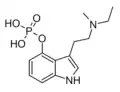

| Psilocybin | Fungi | 4-OPO3H2 | CH3 | CH3 | 4-phosphoryloxy-N,N-dimethyltryptamine | 520-52-5 |